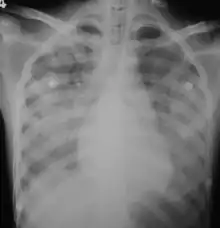

Imaging

In those who have lung involvement, a chest X-ray may demonstrate diffuse alveolar opacities.[20]